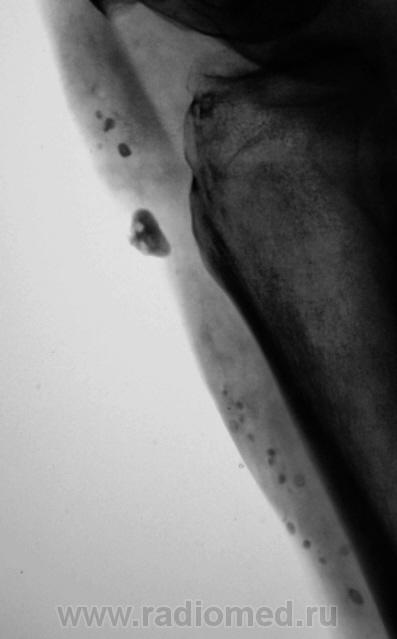

Пациентка направлена в рентгеновский кабинет на рентгенографию коленного сустава в диагнозом - "Артроз".

А как выглядят кожные покровы над этими включениями?

Совершенно обчные, как и на другой ноге.

Валентин Львович, может это быть хондроматозом? И есть гонартроз+медиальный эпикондилит.

Да я не думаю, что это хондроматоз, пока сам в нерешительности, решил послушать мнения коллег.

А пальпаторно есть уплотнения?

А может это быть гемангиомой с ангиолитами?

Гонартроз 2 стадия.Обызвествление параартикулярных мягких тканей .Хондроматоз несколько по-другому выглядит и локализуется более скученно в слизистой сумке.Часто встечала в локтевом и плечевом суставах, в коленном ни разу не видела.

Если это системный процесс (метаб. кальциноз), то то же самое было бы и на снимках локт сустава? Крупное костное тело - сесамовидная кость либо  привет от Осгуд-Шлаттера. Насчет мелких - кроме цистицеркоза ничего в голову не приходит.